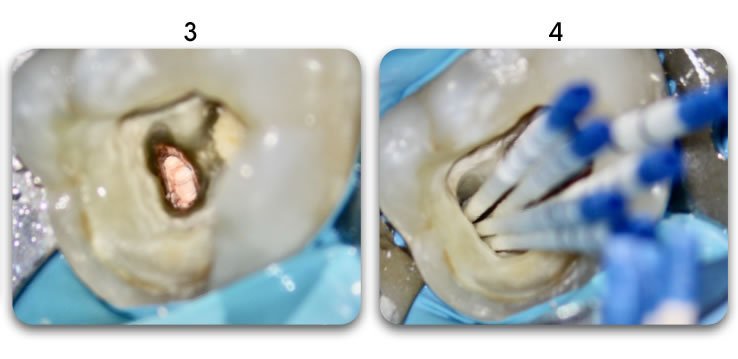

YES. Biolight® DRILL-FREE provides a solid, anatomical anchoring to remaining tooth structure. By arranging reinforcement towards the periphery of the canal walls, support of the core is improved. The concept is similar to how reinforcement steel rods and used in concrete structures, where many smaller rods are placed around the perimeter of the concrete. In addition, all risks associated with drilling are eliminated.

Biolight® DRILL-FREE posts are available in bundles of 4, 6, 9 and 12 strands. The post size is selected based on the width of the canal at the coronal area. Depending upon the canal width at the apical stop, a certain number of strands must be pushed to the stop. Both of the measurements are made with the assistance of a radiograph and the template that is included in the TRAINING KIT.

It is important to follow the steps in the instructional video. There is a procedure that will ensure predictable, bubble-free results (see 1:57 in the video).